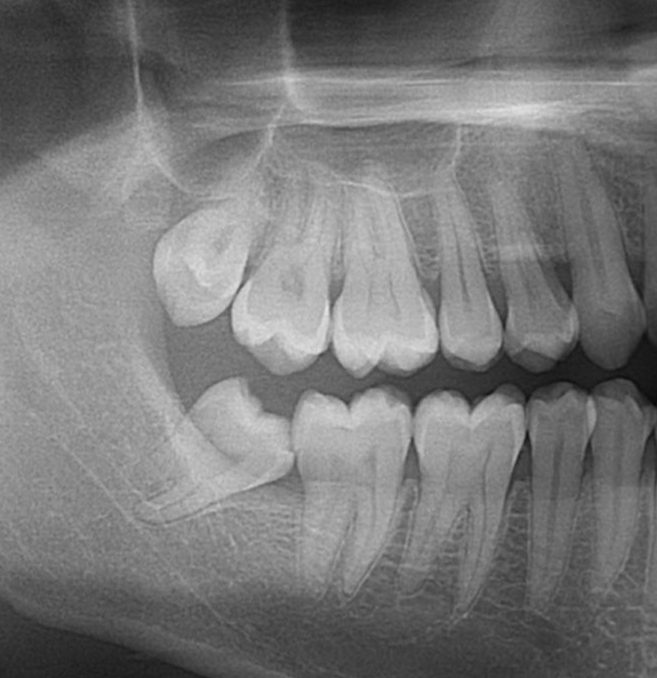

Wisdom tooth close to the Nerve

Patient was having gum swelling and discomfort caused by her lower wisdom tooth.  The wisdom tooth was in close proximity to the Inferior Alveolar Nerve (IAN.)   A 3D scan was taken to make sure the nerve would not be damaged.  The tooth also had very thin roots that could fracture during the extraction.  This wisdom tooth was carefully extracted in our office, avoiding all complications.